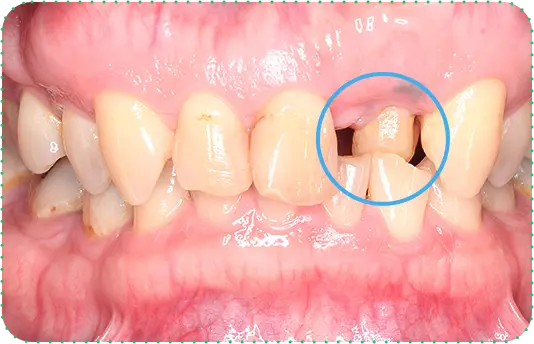

主訴

上の前歯が抜けそう

治療期間

6か月

治療費

30万円

治療内容

右上1番を抜歯後に骨と歯茎を増やし、隣の歯の裏側を少量削り、接着性ブリッジにて修復

治療のリスク

咬み合わせによっては、セラミックが欠ける可能性があります。